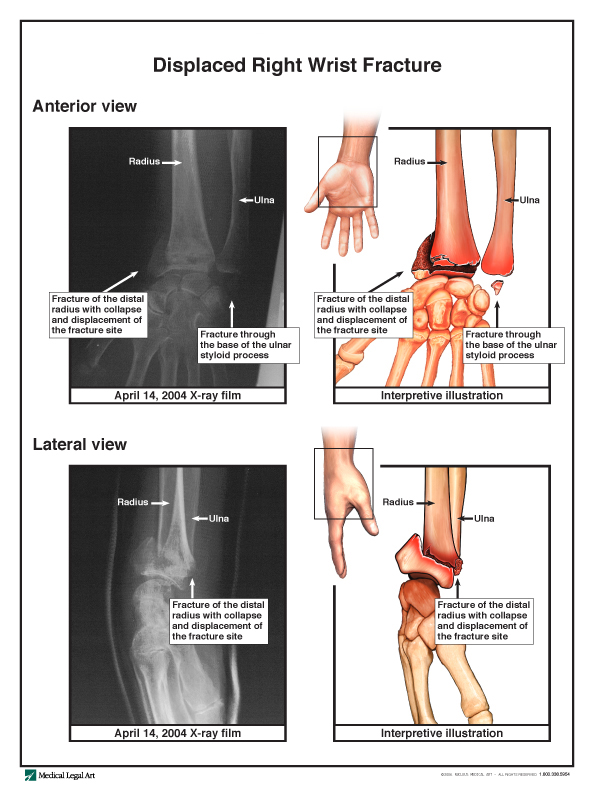

Impairment caused by the right wrist fracture caused her to have significant problems. Before the fall, the patient could ambulate, eat, position, and toilet herself without assistance. After the fall, she required assistance in all of these areas. Her injuries also prevented her from drinking enough fluids without assistance, as she had done before the injury. Yet, the nursing home consistently failed to provide the patient with enough liquids to drink, resulting in dehydration, a urinary tract infection, and an eight-day hospitalization. The patient was transferred to another nursing home when she was released from the hospital and died two years later of unrelaed medical problems. The jury returned a verdict for $1 million on claims for the nursing home’s negligence, fraud, and violations of the Virginia Consumer Protection Act.